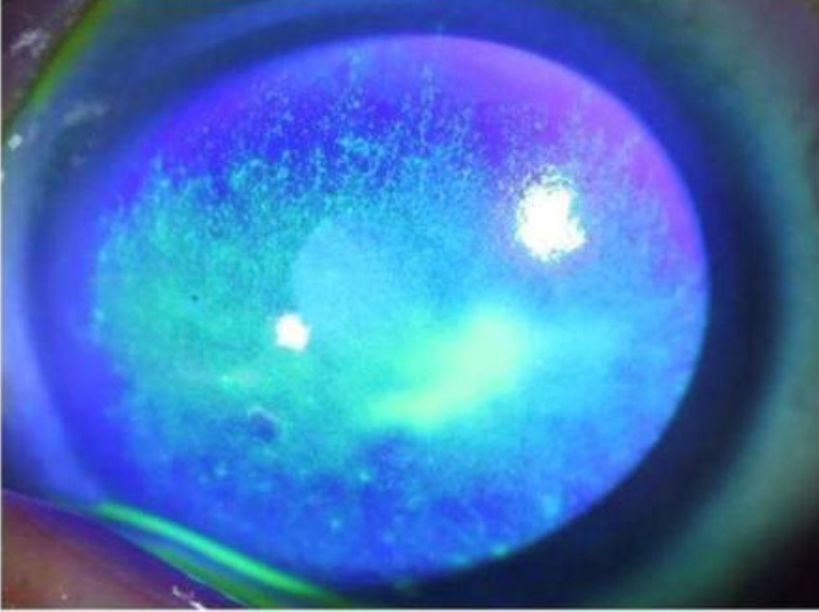

接诊的是眼底病专科副主任孙长文副主任医师,检查后发现林先生双眼角膜弥漫点状上皮脱落(如同湿润的河床干涩裂开),追问病史,原来林先生最近每天使用眼贴敷眼,考虑是眼贴药物刺激所致。

正常角膜染色后

染色部分为上皮缺损脱落的部位